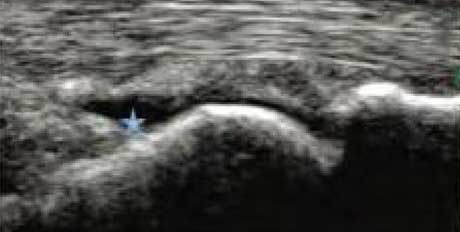

类风湿性关节炎以滑膜炎为基本病理改变,超声可观测到关节暗区的范围及厚度,判断有无滑膜增厚、显示不同程度的滑膜均匀或不均匀增厚,分辨滑膜呈绒毛状、团状或结节状结构向关节腔突起的形态。通过对滑膜厚度、水肿、炎性细胞浸润状况的分级、定量评估RA关节内滑膜的炎性程度。

Ⅰ级滑膜增生

轻度滑膜增生,不超过骨面点连线

Ⅱ级滑膜增生

滑膜增生超过骨面点连线,呈绒毛状,但不越过骨干

Ⅲ级滑膜增生

滑膜增生超过骨面点连线,呈团块状延伸超过一侧骨干